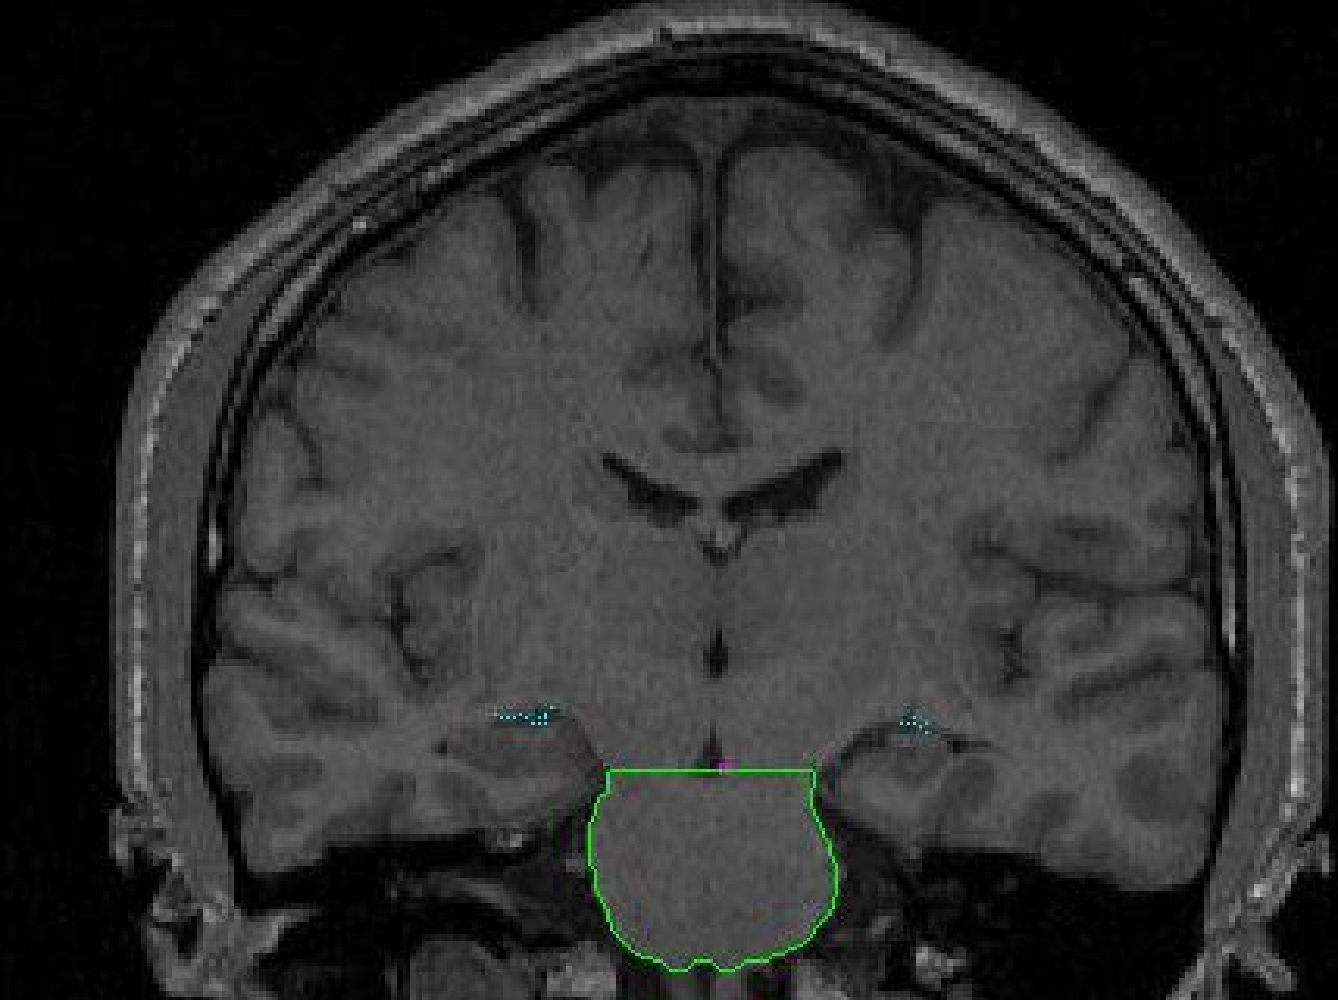

The inferior brainstem line extends from the obex (bottom) of the fourth ventricle

across the width of the brainstem to the pyramidal decussation (bottom of the

pyramidal tracts). In coronal sections this line will mark the inferior border

of the brainstem from the spinal cord.

Part II - Anterior portion of the brainstem

1. Begin segmenting the brainstem when the first slice containing the brainstem is visible. Use the contour function (C) to create a contour that hugs the area of the brainstem. The draw function will also need to be used to connect parts of the contour that are not connected, or to exclude non-brainstem parts from the outline. It may be necessary to use the piece-wise contour method (V) on certain areas of the brainstem.

The inferior border in the anterior extent (around the pons and medulla) is

visible and can be discerned with the contour function.